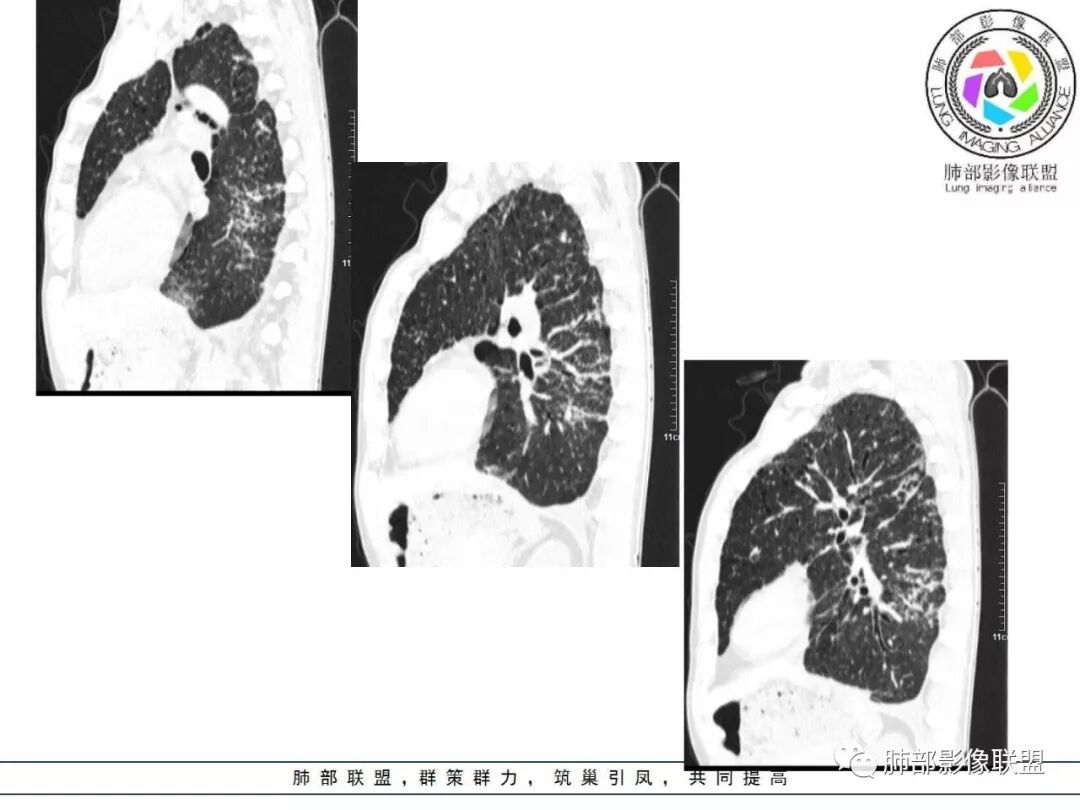

双肺间质性病变,中央间质增厚,胸膜下间质增厚,左侧胸膜肥厚,胸廓变小,肋间隙变窄。

对,大的支气管血管周围

胸部CT:两肺弥漫病灶,磨玻璃影,少许实变,部分累及胸膜,磨玻璃区可见囊?少许胸腔积液,两肺可见结节,支气管血管束增粗,小叶间隔增厚,支气管走形有扭曲扩张,可见纤维化。气肿、大泡。考虑:感染性病变,PCP?查下HIV,CD4,G等。鉴别结核、结缔组织病肺浸润。

患者中年男性,发热1月,体温38℃-39℃,峰值40℃,无畏寒、寒战,伴黄痰,CRP升高明显,降钙素原稍升高,血沉、血糖正常。胸部CT:两肺弥漫病变,磨玻璃影+点片渗出,部分累及胸膜,磨玻璃区边界清楚,少许胸腔积液,两肺支气管血管束增粗,小叶间隔增厚,部分支气管走形有扭曲扩张,可见肺气肿、右肺尖肺大泡及部分纤维化改变。综合考虑:感染性病变。结核或PCP可能性大,鉴别风湿免疫、结缔组织疾病肺浸润和腺癌等恶性病变。

胸部CT:两肺弥漫病灶,中央间质分布为主,部分位于胸膜及叶间裂旁,磨玻璃影,斑片影,部分实性结节,肺气囊,支气管血管束增粗,小叶间隔增厚,叶间裂不均匀增厚,支气管走形有扭曲扩张,可见纤维化、气肿、大泡。考虑:LIP加MALT。鉴别PLCH、PCP、结核、结缔组织病肺浸润。

双肺弥漫性病变,多发磨玻璃密度及小叶间隔增厚,大部分沿支气管血管束分布,伴支气管轻度扩张,以午后及晚上发热为主,考虑感染性病变,间质性结核可能大,另双肺多发肺气囊,LIP待排

病灶呈片状磨玻璃密度影,呈典型的烟花征。磨玻璃影密度偏高,有网结节样改变,与正常肺实质分界清楚,且常见相对高密度的勾画。

烟花征分为3肿类型:晕征、反晕征及均匀分布。

病变一般沿血管支气管束分布或小叶分布,一般上肺多于下肺(这与常见继发性肺结核分布相若)。

常会伴有其他继发性肺结核病灶,如斑片影、结节影,树芽征,新旧不等改变。

2. 肺气肿背景(小叶中心性肺气肿);双肺多发病灶整体沿血管支气管束及胸膜下分布,以上叶及下叶背段分布为主,有实变及GGO,边界清楚,有树芽,小叶间隔及中央间质增厚,叶间裂见到多发结节,部分支气管不规则牵拉扩张,提示病灶纤维化明显,结合临床病史,考虑病灶为间质性感染,肺门及纵隔内有钙化淋巴结,小叶间隔结节,考虑淋巴道增值性疾病可能,综合常规要怀疑间质性肺结核。